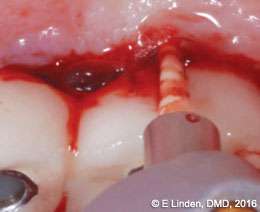

Fiberotomy: After bone sounding was complete, the modified fiberotomy procedure was performed (Figure 8). A small elevator was used to sever gingival fibers around the affected implants in order to open up the coronal aspect of the crest of gingival tissue (2 mm-4 mm deep). This step is important as it helps to introduce the laser tip into the pocket, ensuring the most efficient delivery of the laser energy to the target tissue.